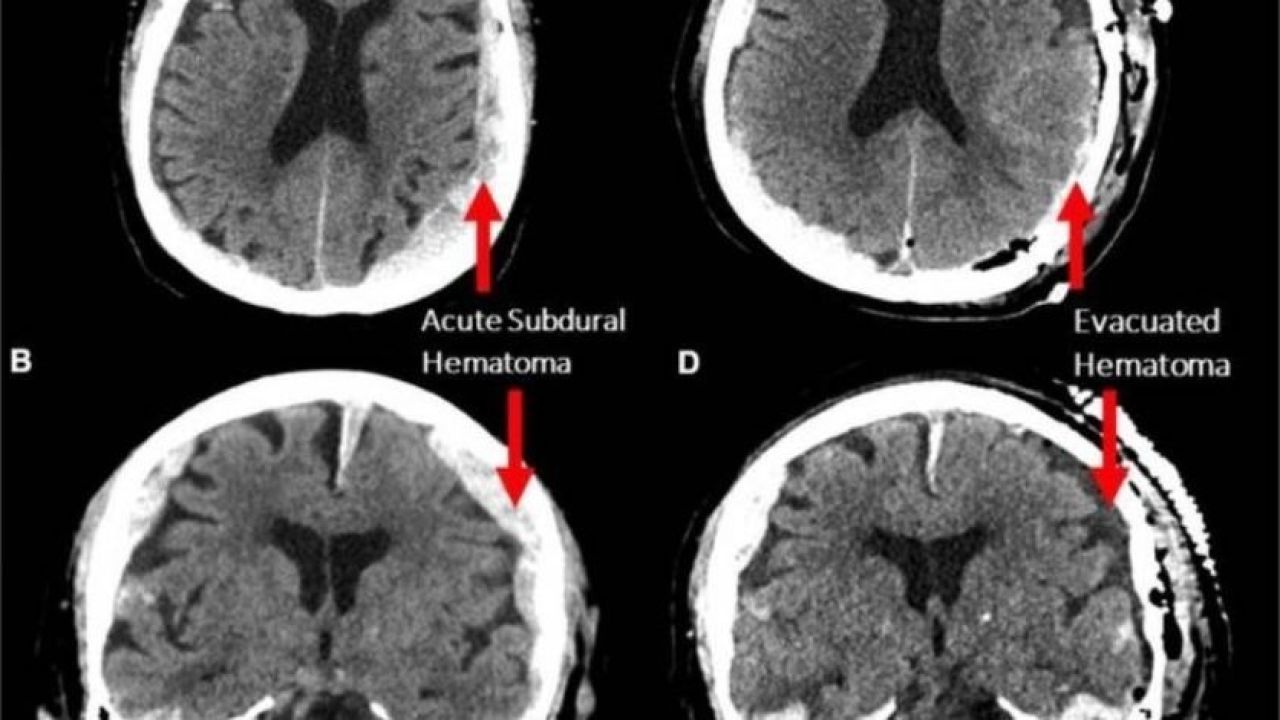

Bu kapsamda 87 yaşındaki bir epilepsi hastasının kalp krizi geçirmesinin ardından ölümünün gerçekleştiği sırada kayıtta olan Elektroensefalografi (EEG) sayesinde beyin hareketliliği incelendi.